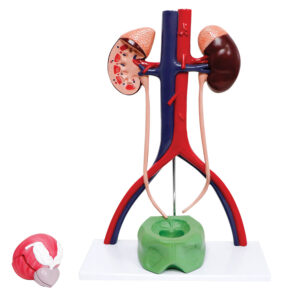

Modelo do sistema urinário